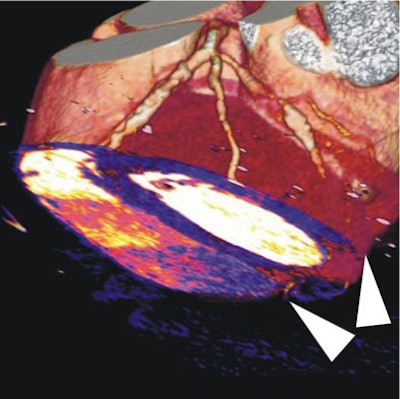

| In a 64-year-old man with chest pain, colored regions of blood-pool images represent iodine, while the darker parts of the myocardium depict ischemia as a lack of contrast uptake. Arrows indicate the myocardial blood-pool deficit, i.e., ischemia. |